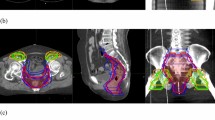

The methods relative to lymphoscintigraphy, surgical removal and histopathological examination of sentinel LNs have been already described14,15. Patients after positioning in supine position on Comby-Fix® underwent a contrast-enhanced CT and FDG-PET simulation. FDG-PET was used both for staging and target definition. CTV included the GTV (primary tumour and any positive LNs), the ischiorectal fossa, the mesorectum, and the internal and common iliac LNs until the L5-S1 space.

As the inguinal LNs irradiation is the standard treatment in anal cancer, all patients enrolled in this study with positive SLNB were treated on groin. Patients who had negative SLNB and negative imaging in inguinal region were considered for RT without groin irradiation, so as to spare inguinal toxicity; patients were also involved in the final clinical decision. PTV1 and PTV2 were defined as GTV and CTV, expanded with a margin of 0.5 cm, respectively. Median prescribed dose was 50.4 Gy in 28 fractions (1.8 Gy/fraction) to the PTV2, and 64.8 Gy in 36 fractions, delivered as sequential or concomitant boost, to the PTV1. RT techniques consisted of 3DCRT or IMRT (Volumetric Modulated Arc Therapy (VMAT) Rapid Arc or Helical Tomotherapy). The planned concomitant chemotherapy schedule was continuous infusion 5-FU 1,000 mg/mq2 delivered from day 1 to 4 and from day 29 to 32 combined to Mitomycin-C 10 mg/m2 delivered on day 1 to 29.